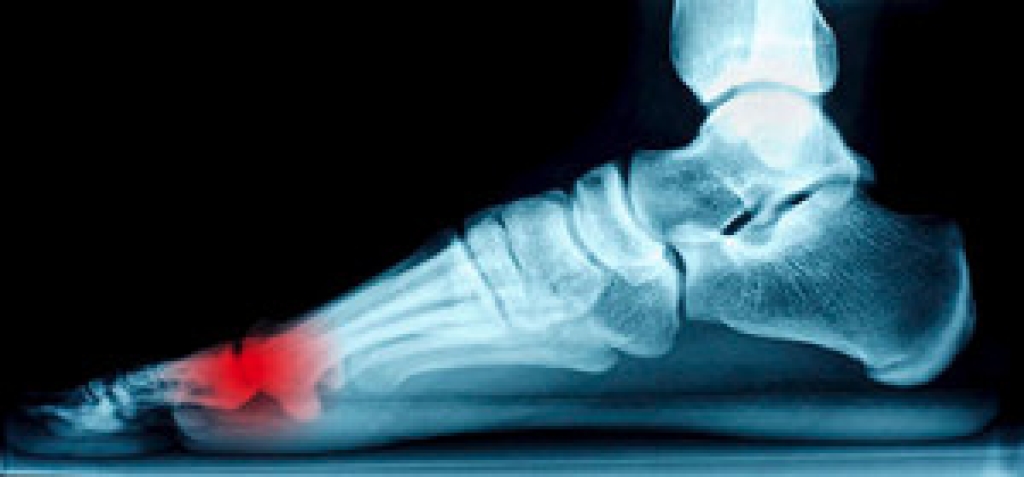

The ankle-brachial index (ABI) is a screening tool used to identify peripheral artery disease, a condition that causes poor circulation in the lower limbs. The ABI is a simple measure that involves taking the blood pressure at the arm and at the ankle and comparing the two numbers to determine the patient’s risk of having peripheral artery disease. This is most frequently done using a blood pressure cuff and a Doppler ultrasound instrument. Some doctors may do the ABI using an automated device instead. Regardless of the method used to obtain this reading, the ABI is quick, noninvasive, and virtually painless. If you suspect that you may have poor circulation in your feet and ankles, please consult with a podiatrist who can screen you for peripheral artery disease.

Vascular testing checks for how well blood circulation is in the veins and arteries. This is most often done to determine and treat a patient for peripheral artery disease (PAD), stroke, and aneurysms. Podiatrists utilize vascular testing when a patient has symptoms of PAD or if they believe they might. If a patient has diabetes, a podiatrist may determine a vascular test to be prudent to check for poor blood circulation.